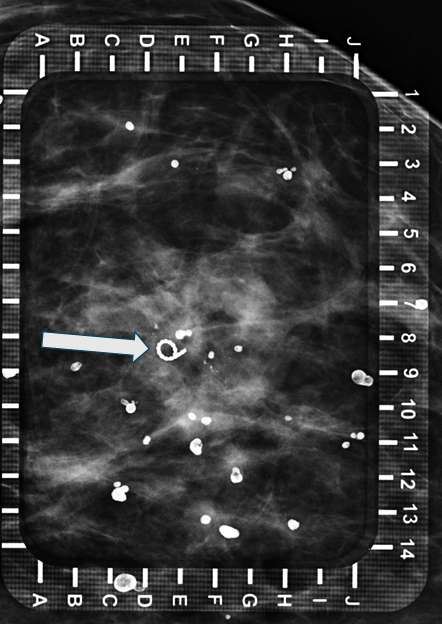

Technologist places breast in compression with fenestrated alphanumeric grid paddle. Technologist then takes a scout image to confirm appropriate grid placement overlying the target (Figure 1).

Radiologist confirms appropriate compression of breast tissue, appropriate visualization of biopsy target, and performs adjustments if necessary. Radiologist identifies target site to determine alphanumeric grid coordinates.